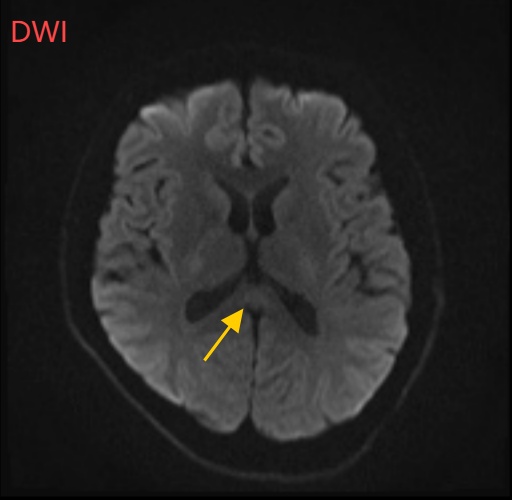

小董的影像结果显示,胼胝体压部发生病变

胼胝体压部("压部")是大脑里的“视觉总监”,眼睛所看到的信息传送到大脑后,由它负责反应整合成图像在脑海中呈现。“压部”发生病变后,就像电视机信号接收不良,屏幕出现雪花一样,眼睛视物就会受到影响。除了“压部”,胼胝体的其他部位也有病变,所以小董才会出现幻听、手抖等症状。

经过一周治疗,小董的胼胝体压部病变明显好转